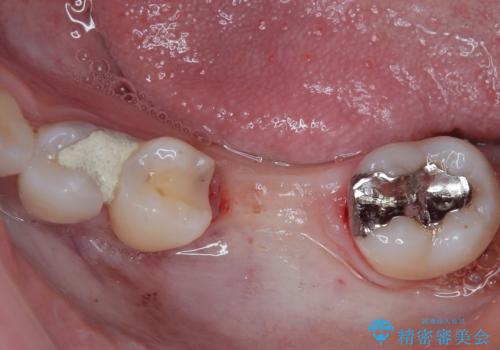

- ブリッジの歯のないところにインプラントを入れて、銀歯を白くやり替えたいと来院された患者様です。

歯の欠損している箇所にはインプラント治療をし、銀歯と仮詰めの部分はセラミックインレーにて補綴することとしました。

すべての治療の前に親知らずの抜歯も行っています。